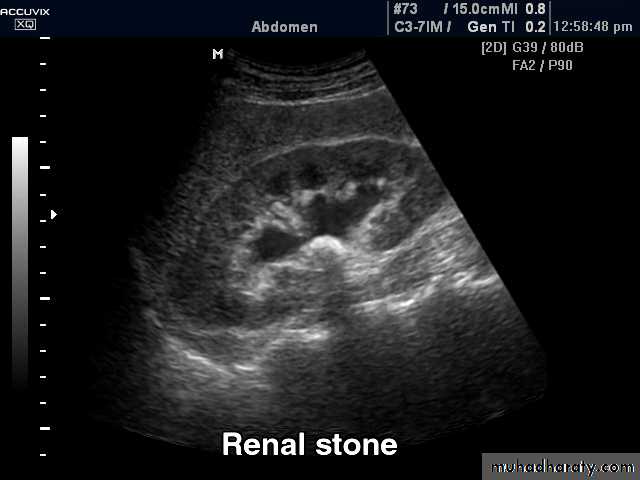

Ultrasonography:

Investigate patients with symptoms thought to arise from the urinary tract.

Demonstrate the size of the kidneys and exclude hydronephrosis in patients with renal failure.

Diagnose hydronephrosis, renal tumours, abscesses and cysts including polycystic disease.

Urinary calculi